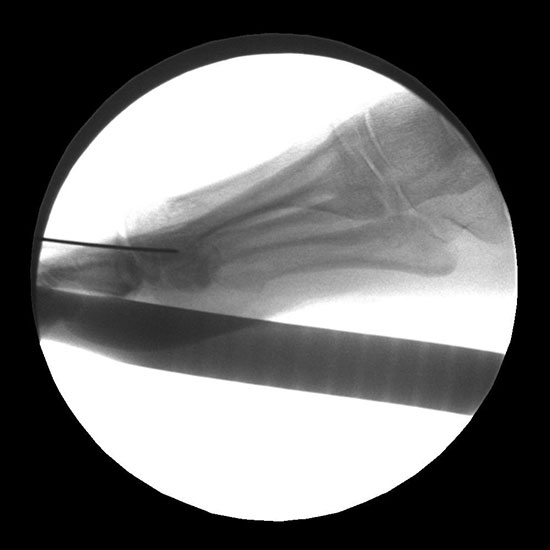

• Bildverstärker (idealerweise Fluoroskop mit niedriger Strahlenbelastung).

Es erfolgt dann die Osteotomie des Köpfchens im dorsalen ¼ des Köpfchens, parallel zur simulierten Bodenauftrittsfläche. Es ist streng darauf zu achten, dass es zu keiner Plantarisierung des Köpfchens kommt. Die Hohmann-Haken müssen so gesetzt werden, dass sie die Strecksehnen während der Osteotomie schützen. Während des Sägevorgangs ist eine entsprechende Stellungskorrektur der Hohmann-Haken durchzuführen um eine komplette Osteotomie zu gewährleisten. Der Winkel des Sägeschnittes bei MT II beträgt ca. 45° zur Schaftachse und nimmt im weiteren Verlauf zu den lateralen Metatarsalia auf ca. 20° ab. Die Osteotomien werden dementsprechend länger. Kommt es zu einer Verletzung der langen Strecksehne, muß diese dann wieder durch eine spannungsfreie Naht rekonstruiert werden. Dieser Schritt ist der entscheidende für den Erfolg der Operation und ist mit der entsprechenden Sorgfalt und Planung durchzuführen.

Darstellung des Sägeschnittes im dorsalen Drittel des Metatarsaleköpfchens.

Die Osteotomie wird nun mit einem Meißel Stärke 10 mm dargestellt, das mobilisierte Köpfchen nach plantar gedrückt. Durch eine leicht nach proximal abfallende Osteotomie erfolgt die Bestimmung der Verkürzung und das Ausmaß der Verschiebung des Köpfchens nach dorsal. Zur Vermeidung einer Plantarisierung des Köpfchens durch die Verschiebeosteotomie erfolgt ein 2. paralleler Sägeschnitt mit Resektion einer 2-3 mm dicken Knochenscheibe.

Durch eine maximale Plantarflexion der Zehe kommt es zu einer Reposition des osteotomierten Köpfchens, da die intakten Seitenbänder einen entsprechenden Zug ausüben. Dies kann noch durch einen retrokapitalen Druck unterstützt werden. Das Köpfchen wird mit einer entsprechend großen Klemme oder Fasszange positioniert, unter Berücksichtigung einer eventuell notwendigen Rotationskorrektur. Bei korrekter Gelenkflächenstellung wird die Osteotomie komprimiert, hierbei ist dringend darauf zu achten, dass die Hohmann-Haken nicht im Spalt der Osteotomie einen kompletten Knochenkontakt des Köpfchens verhindern. Dies ist vermutlich der Hauptgrund für verzögerte Knochenheilungen oder Luxationen des Köpfchens in der Aufbelastungsphase. Sofern diese Punkte kontrolliert wurden erfolgt die Fixation des Köpfchens, hier durch Vorbohren mit einem 1,6 mm Draht und einer 2,0 mm Titanschraube.